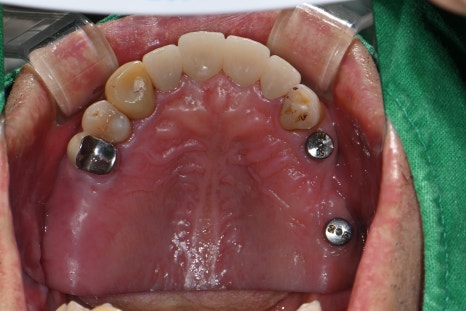

⚙️ 어금니 임플란트 보철까지 완성

뼈이식과 임플란트를 성공적으로 마친 후,

구강스캐너로 정밀하게 보철물을 제작하여 저작기능을 회복시켜드렸습니다.

서울오브치과병원은 모든 임플란트 보철을 내부에서 직접 설계·제작하여

정밀도와 맞춤도 면에서 더욱 뛰어난 결과를 자랑합니다.

🖼️ 어금니 임플란트 보철 완성 사진

디지털 스캔으로 미리 설계된 임플란트 보철물 / 구강 내 실제 setting 된 모습